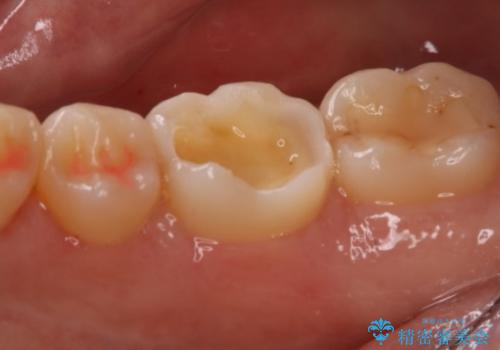

- 右下奥歯の虫歯治療を希望された患者様です。

保険の材料が劣化し、直下で虫歯の存在が確認出来ました。

セラミックを希望されたので形態・切削量を考慮し、セラミックインレーでの治療を計画しました。

虫歯が広く進行していましたが神経には到達していなかったので、予定通りセラミックインレーでの治療を行いました。